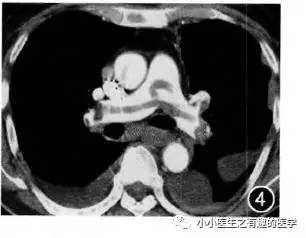

病例四:

老人,吸烟30年。胸闷、呼吸困难1年。当地医院反复治疗,近期症状加重。

最终诊断:肺栓塞。